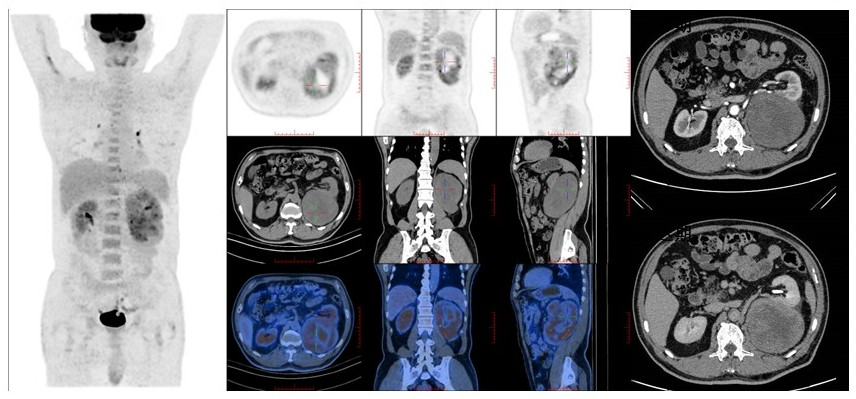

病例(9为一老年女性,体检发现左肾上腺肿物就诊既往高血压病史;实验室检查示醛固酮/肾素比值稍高,血钾稍减低;增强CT肿物呈明显不均匀强化;18F-FDG PET/CT示肿物代谢不均匀明显增高;(左肾上腺肿物)切除病理为肾上腺皮质腺癌

9. 71岁,体检发现左侧肾上腺肿物肾上腺皮质腺癌